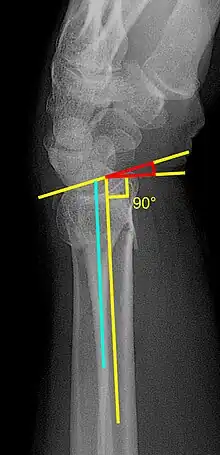

| A Colles fracture as seen on X-ray: It is a type of distal radius fracture. | |

Diagnosis may be evident clinically when the distal radius is deformed, but should be confirmed by X-ray. The differential diagnosis includes scaphoid fractures and wrist dislocations, which can also co-exist with a distal radius fracture. Occasionally, fractures may not be seen on X-rays immediately after the injury. Delayed X-rays, X-ray computed tomography (CT scan), or Magnetic resonance imaging (MRI) can confirm the diagnosis.

X-ray of the affected wrist is required if a fracture is suspected. Posteroanterior, lateral, and oblique views can be used together to describe the fracture.[5] X-ray of the uninjured wrist should also be taken to determine if any normal anatomic variations exist before surgery.[5]

Various kinds of information can be obtained from X-rays of the wrist:[5]

- Volar or dorsal tilt - A line is drawn joining the most distal ends of the volar and dorsal side of the radius. Another line perpendicular to the longitudinal axis of the radius is drawn. The angle between the two lines is the angle of volar or dorsal tilt of the wrist. Measurement of volar or dorsal tilt should be made in true lateral view of the wrist because pronation of the forearm reduces the volar tilt and supination increases it. When dorsal tilt is more than 11 degrees, it is associated with loss of grip strength and loss of wrist flexion.[5]

- Radial inclination - It is the angle between a line drawn from the radial styloid to the medial end of the articular surface of the radius and a line drawn perpendicular to the long axis of the radius. Loss of radial inclination is associated with loss of grip strength.[5]

- Radial length - It is the vertical distance in millimetres between a line tangential to the articular surface of the ulna and a tangential line drawn at the most distal point of radius (radial styloid). Shortening of radial length more than 4mm is associated with wrist pain.[5]

- Ulnar variance - It is the vertical distance between a horizontal line parallel to the articular surface of the radius and another horizontal line drawn parallel to the articular surface of the ulnar head. Positive ulnar variance (ulna appears longer than radius) disturbs the integrity of triangular fibrocartilage complex and is associated with loss of grip strength and wrist pain.[5]